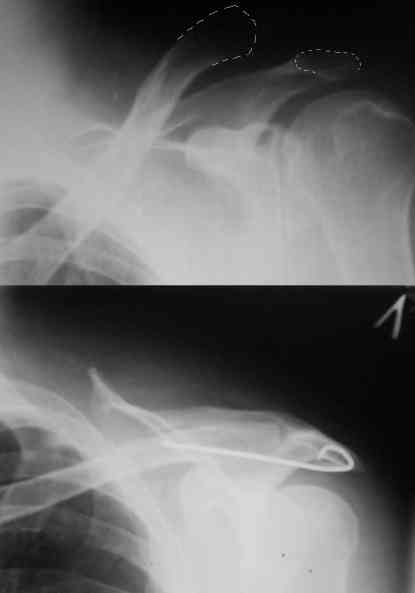

Внешний вид больного (травма: 09.10.2007, операция: 11.10.2007) Ориентиры доступа: овальный – пальпируемый акромиальный конец ключицы, линейный – операционный разрез

Введение крючка в подготовленный канал Дистальная часть крючка подведена под акромион и фиксирована на нем путем загибания (вывих ключицы устранен)